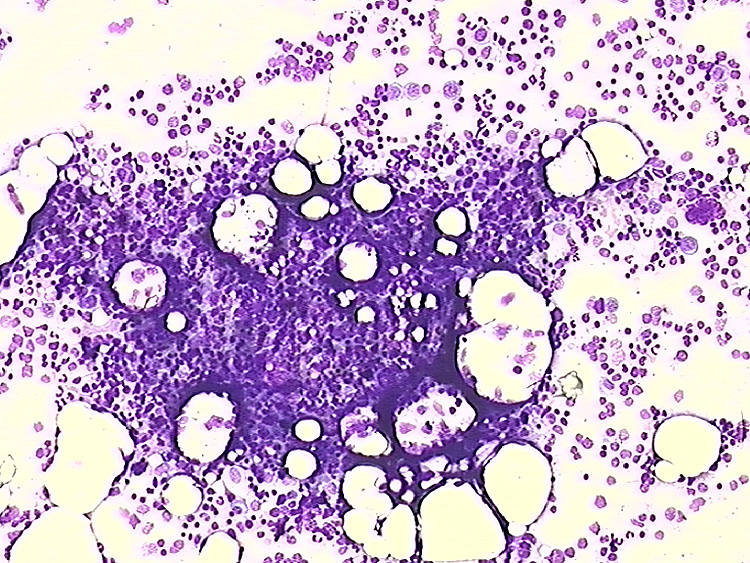

Abb. 1: Übersicht über das Knochenmark

(Mikroskopische Objektivvergrößerung X10)